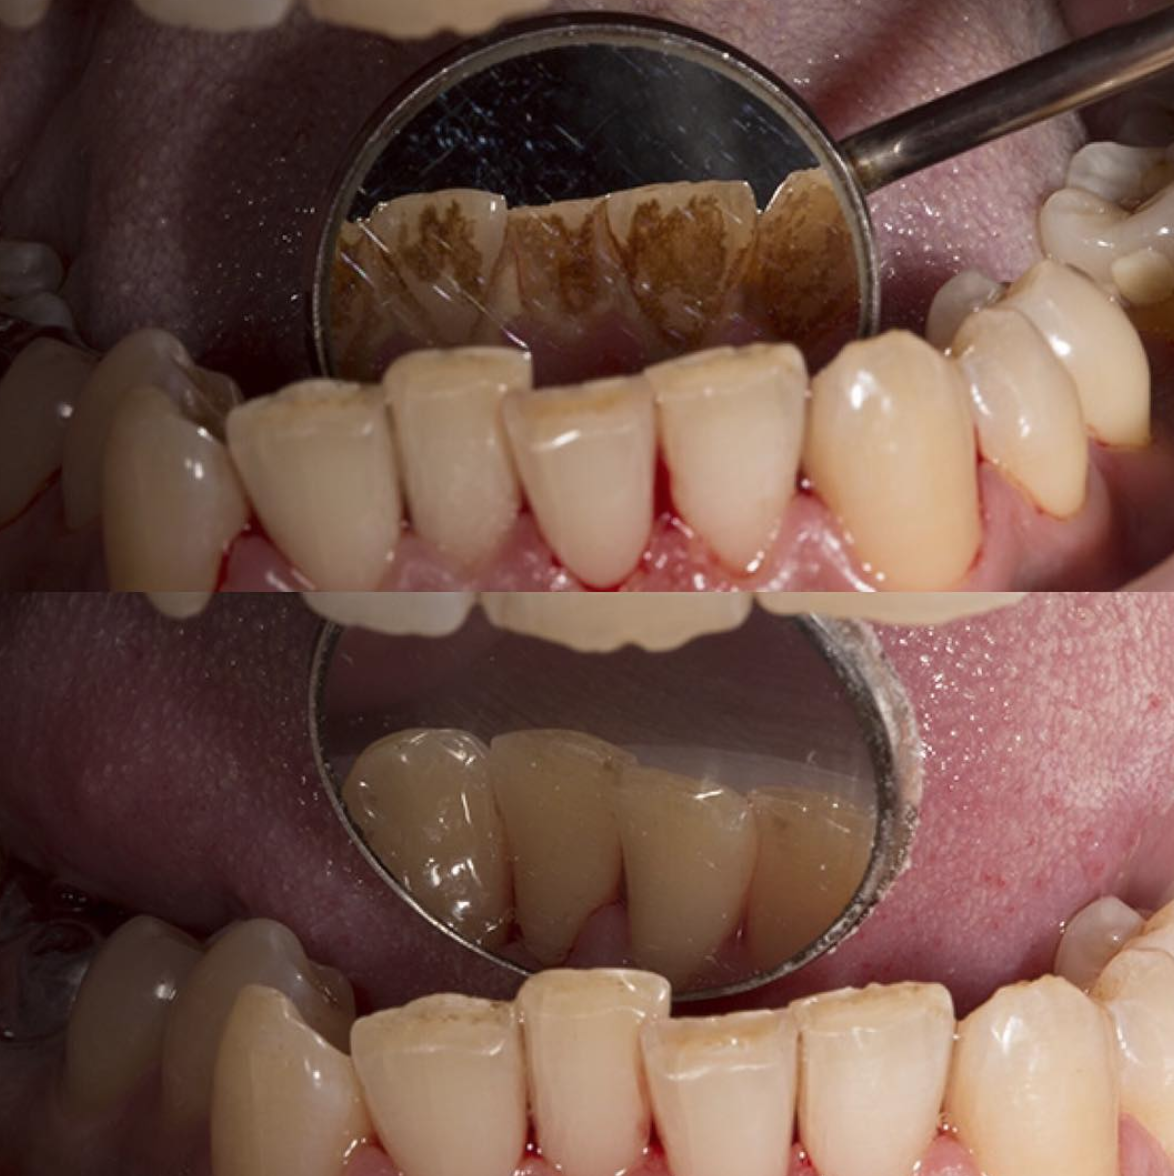

Твердые отложения (зубной камень) образуются в межзубных промежутках, на зубах в придесневой и поддесневой областях. Зубной камень может привести к развитию таких заболеваний, как гингивит, пародонтит или кариес. Процедуру проводят ультразвуковым скейлером, который с помощью вибраций удаляет твердые отложения с поверхности зуба.

Удаление плотного налета, который образуется на зубах при плохой гигиене, вследствие курения или частого употребления чая или кофе проводится с помощью современной системы Air Flow. Специальный аппарат под давлением распыляет на зубы смесь воды и абразивных частиц. В наших клиниках используются самые щадящие порошки, чтобы не повредить поверхность эмали. Чистка Air Flow оказывает также осветляющий эффект — зубы становятся белее на один-два тона.